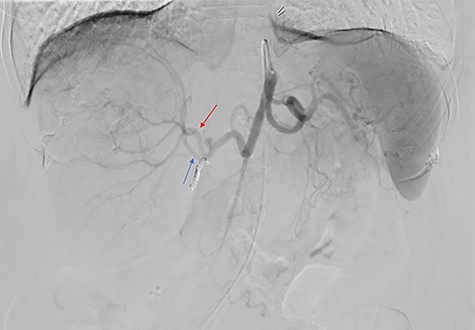

The consensus from the multidisciplinary liver tumor board was to proceed with Y-90 TARE to achieve tumor shrinkage and to induce left liver lobe hypertrophy in preparation for surgical resection. In February 2019, the patient underwent a Y-90 TARE, and a dose of 2.71 GBq (73.4 mCi) of glass microspheres (TheraSpheres, Boston Medical) was injected into the right hepatic artery (Fig. 3). The delivery of the dose was verified using Bremsstrahlung liver SPECT imaging post-injection (Fig. 4). Based on this activity distribution, the dose was calculated on a voxel-by-voxel basis using Sure Plan software (MIM, Cleveland Ohio). The local deposition method (LDM) was used, and the dose was scaled by the amount of activity injected.

Post-Y-90 Bremsstrahlung SPECT/CT demonstrates uptake predominantly within the main right liver lobe lesion (GTV) with minor uptake into the Segment IVA lesion.